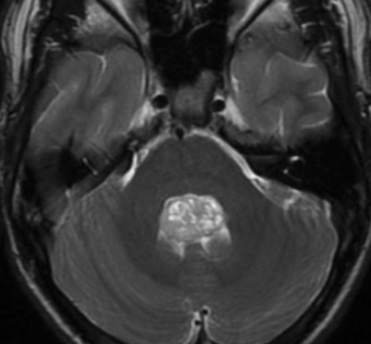

Ependymome (Grade II)

- Pédiatrique ++

- Tumeur du 4e ventricule

- Extension en toothpaste squeeze

- Extension au foramen de Magendie et Lushka ++